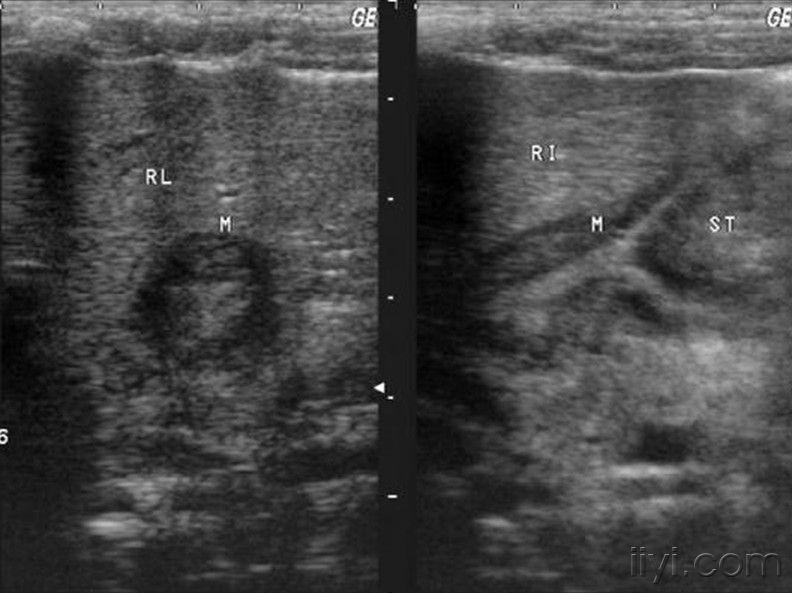

超过上述正常值的情况就可以诊断为肥厚性幽门梗阻.

图片尺寸881x332